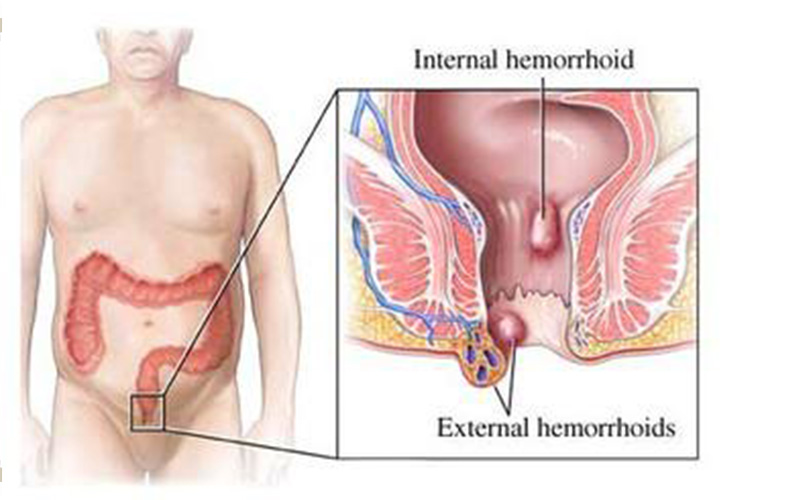

痔瘡與直腸息肉

A:直腸息肉和痔瘡都是比較常見的一類肛腸疾病,這兩者有著明顯的區別,直腸息肉形成的原因和內痔形成的原因是不同的,直腸息肉是指直腸黏膜表面向腸腔內凸起的良性病變,其發生的原因可能是由炎症所導致,也可能是由外傷所導致黏膜出現增生性改變所導致,並且直……

A:直腸息肉和痔瘡在臨床的表現上,都可以在肛門內或者是肛門外摸到質軟的腫物,按壓的時候也沒有疼痛感。大便乾燥的時候這兩種疾病均可以導致一定便血,但是直腸息肉屬於實體腫瘤,發生於直腸的黏膜層。痔瘡屬於血管內病變,它並非實質腫瘤,而是一團增多的血管……